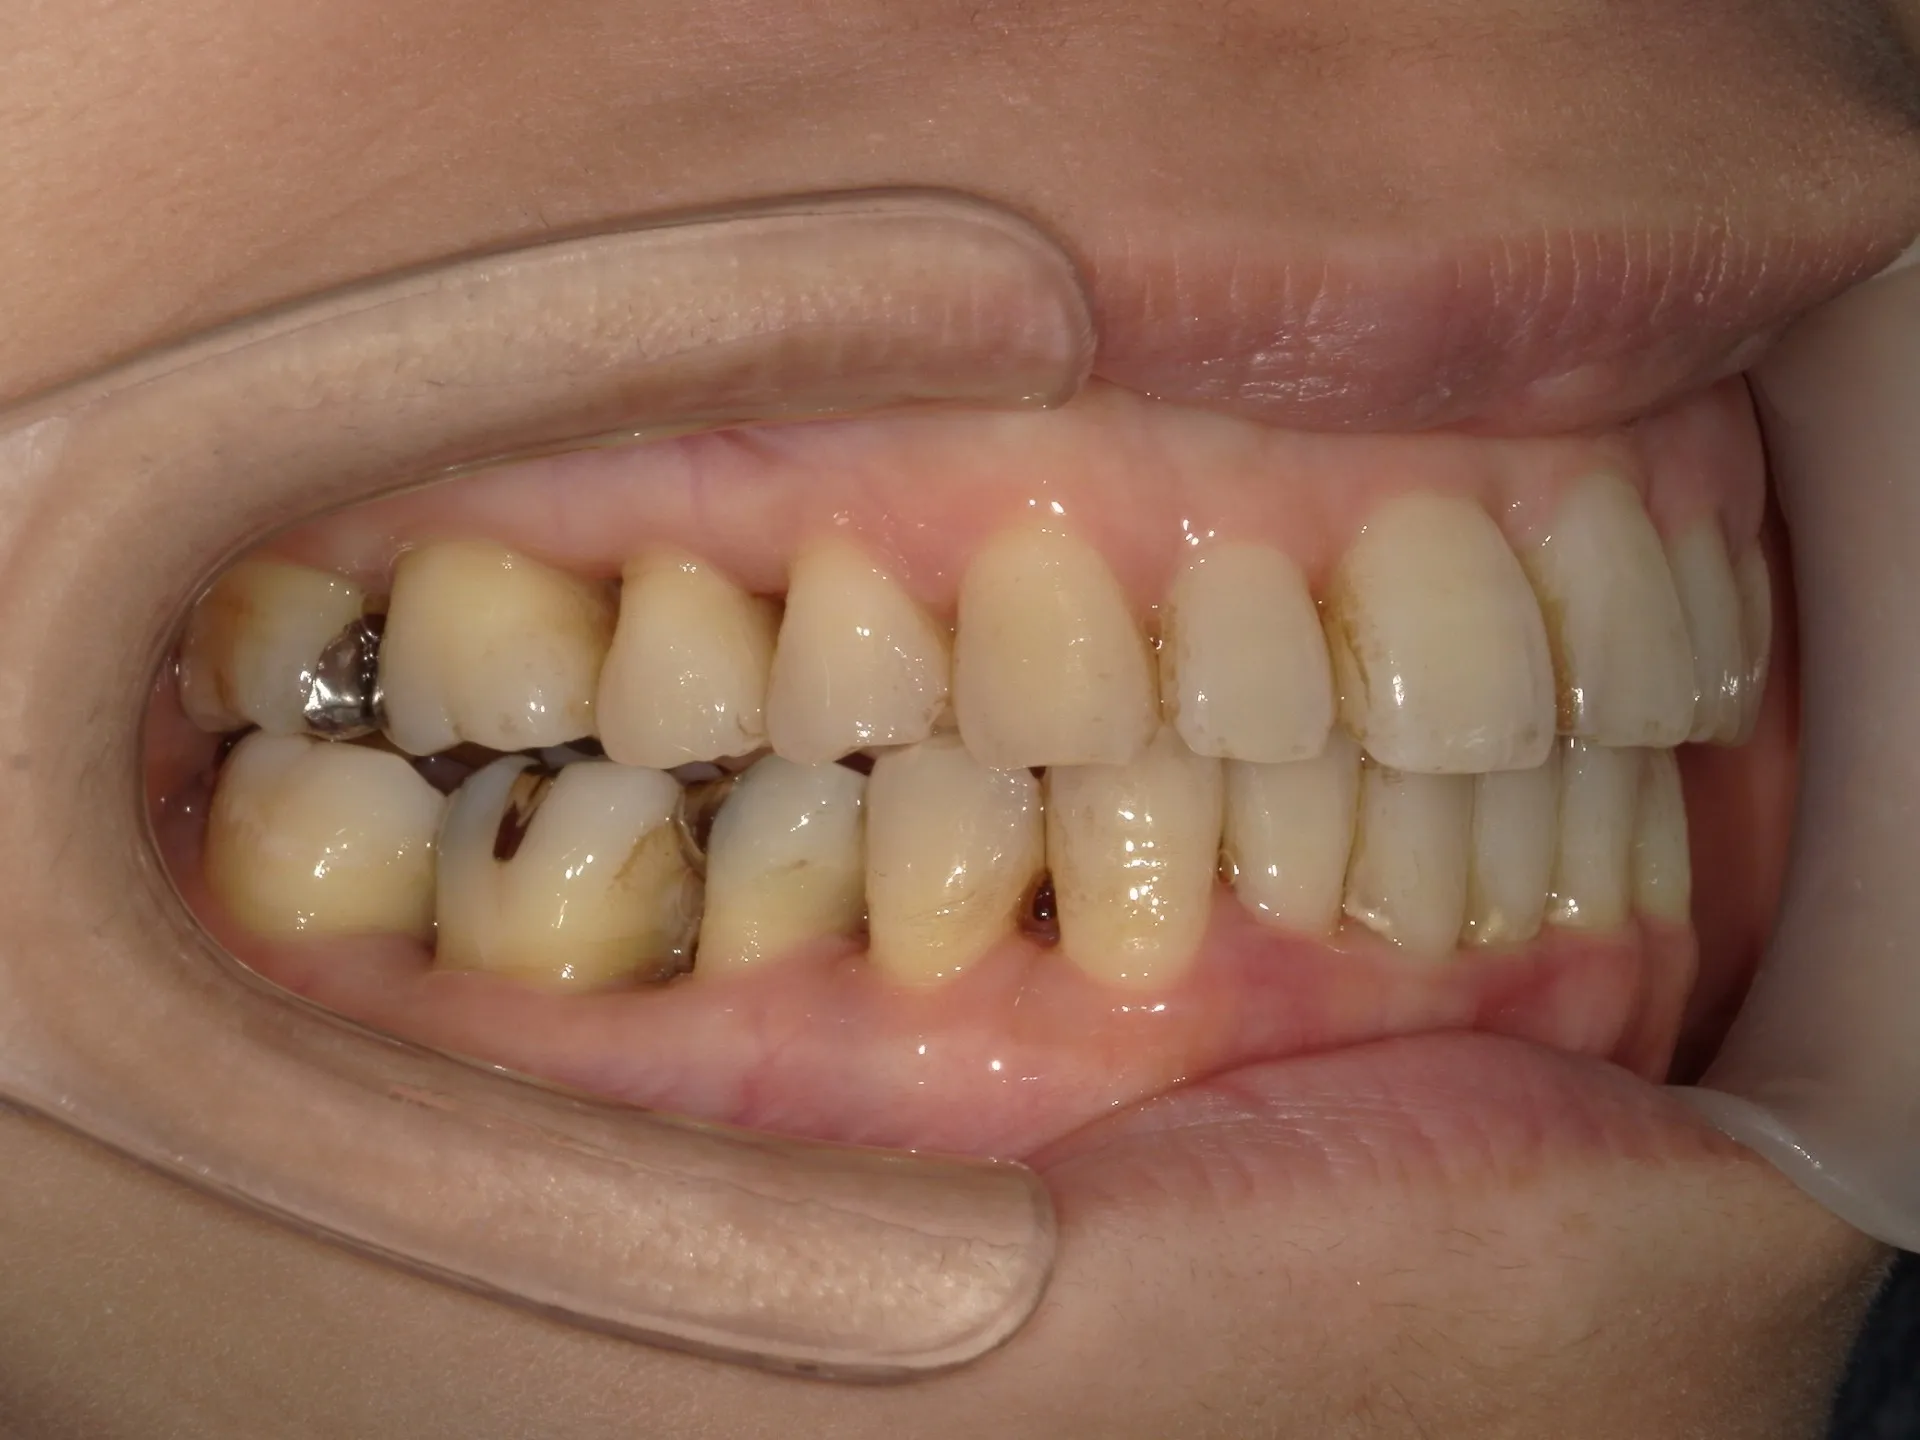

当院では矯正治療と歯周治療を平行して行うことにより矯正治療を進めていけることができました。

しかしながら、今回の治療途中で歯茎が腫れるなどの影響もあり、歯周治療中の矯正治療はリスクであることは患者様にも初回の段階で説明していることもあり、患者様もこの状態の歯並びで満足しており、歯を残すためにも今回は矯正治療を中断する希望をされました。